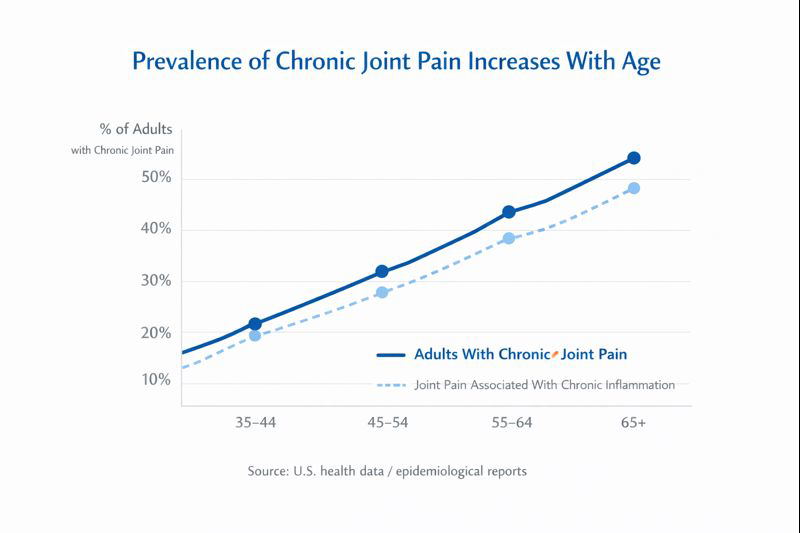

Chronic joint pain has quietly become one of the most widespread physical complaints in the United States. According to health data cited by major medical institutions, an estimated 40% of American adults report persistent joint stiffness, swelling, or recurring pain by age 55 — and this percentage continues to rise each year.